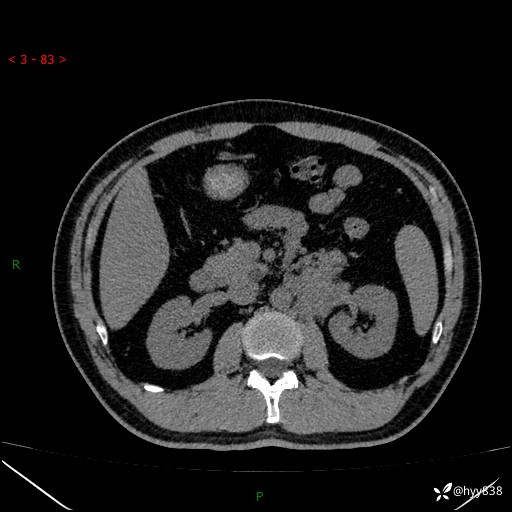

现病史:患者3月余前检查发现左侧腹膜后占位,大小约3.7*4.9cm,平素无腰疼,无肉眼血尿,无尿频尿急等不适,当时未特殊处理,在门诊复查CT提示左侧腹膜后占位,门诊拟“左侧腹膜后占位”收入院。 起病以来,患者精神佳,饮食、睡眠良好,大小便正常,体力体重无明显变化。

腹膜后CT平扫+增强